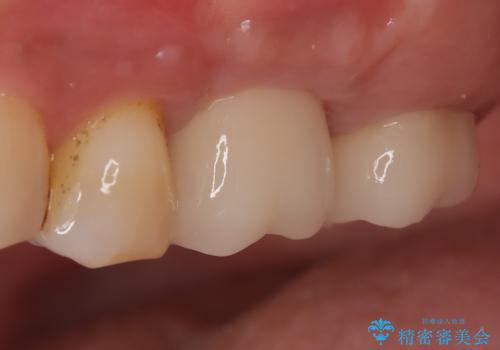

【歯牙破折】インプラントによる咬合回復

歯牙の破折を認めたため抜歯をし、インプラントにて咬合回復をしました。

抜歯後、骨増生を行ったのちインプラントを埋入しています。